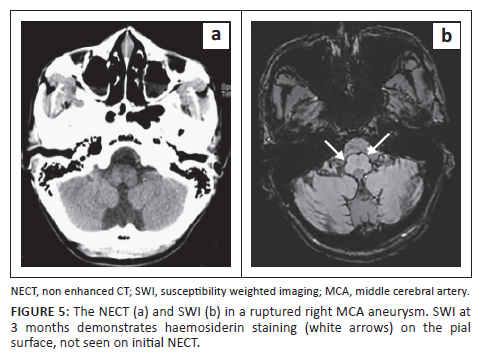

In comparison, the current study showed high haemosiderin detection, with a sensitivity of 86% in the infratentorial compartment, exceeding that of the initially detected haemorrhage on NECT (SWI 11; CT 7) as depicted in Figure 5. This is most likely because of CSF flow as described by Koeppen et al., who showed in CSF flow studies that the brainstem and cerebellar convexities initially receive preferential CSF flow and serve as a site of haemosiderin deposition, albeit remote to the site of rupture. This has been described in patients with recurrent subarachnoid haemorrhage causing superficial haemosiderosis.